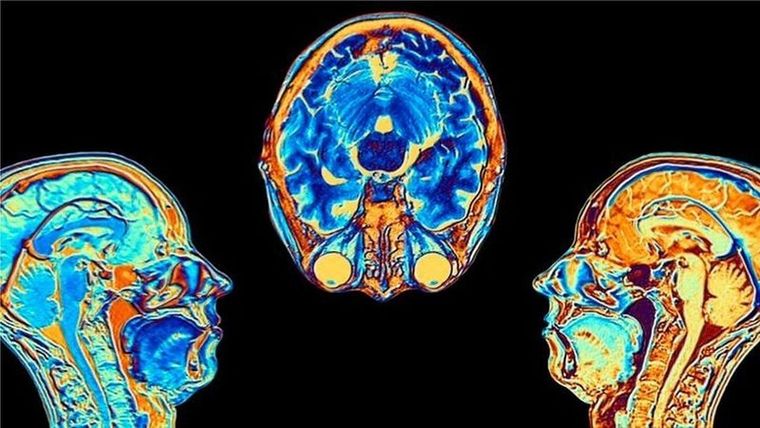

Los investigadores hallaron diferencias significativas en las resonancias magnéticas hechas antes y después de la infección.

Incluso después de una infección leve, las imágenes mostraron que el tamaño total del cerebro se había reducido ligeramente, con menos materia gris en las regiones relacionadas con el olfato y la memoria.

- El tamaño general del cerebro en los participantes infectados se había reducido entre un 0,2 y un 2%

- Hubo pérdidas de materia gris en las áreas olfativas, vinculadas al olfato, y en regiones vinculadas a la memoria.

La pérdida más significativa de materia gris fue en las áreas olfativas, pero no está claro si el virus ataca directamente esta región o si las células simplemente mueren por falta de uso, después de que las personas con covid pierden el sentido del olfato.